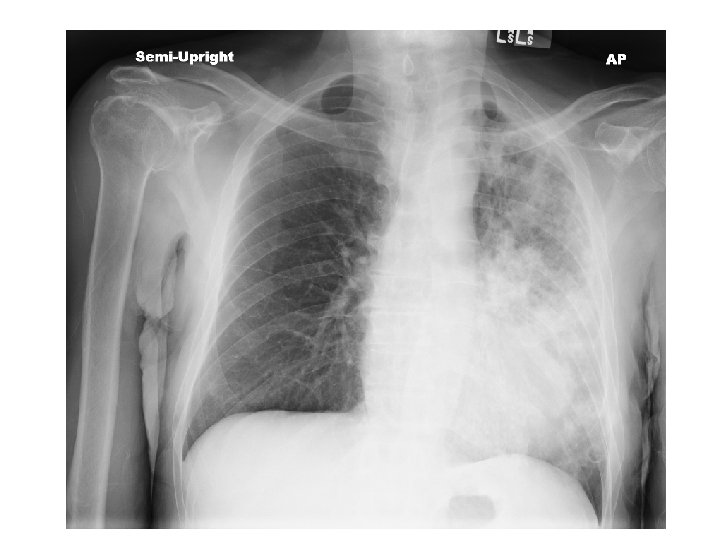

A few hours post-bronchoscopy… • • Tachypneic with RR 30 s Tachycardic to HR 150 s Hypoxic w/ SPO 2 92 on 4 L NC Accessory muscle use. Crackles, most prominent over left upper lung field. Decreased breath sounds, more prominent on left side • ABG 7. 5 / 22 / 65 / 20 / 93, lact 3. 4 • Transferred to MICU for new sepsis secondary to HCAP ; Rx vancomycin and cefepime

Day 6 & 7 • • BAL smear : 4+ AFB isolation re-initiated Started on RIPE Blood and respiratory fungal cultures negative

Chest radiography • Active disease: upper lobe infiltration/ cavity/ effusion • Healed: nodules, fibrotic scars, calcified granulomas or basal pleural effusion • Normal in latent TB • HIV: infiltrate in any lung zone, mediastinal or hilar LAD, normal